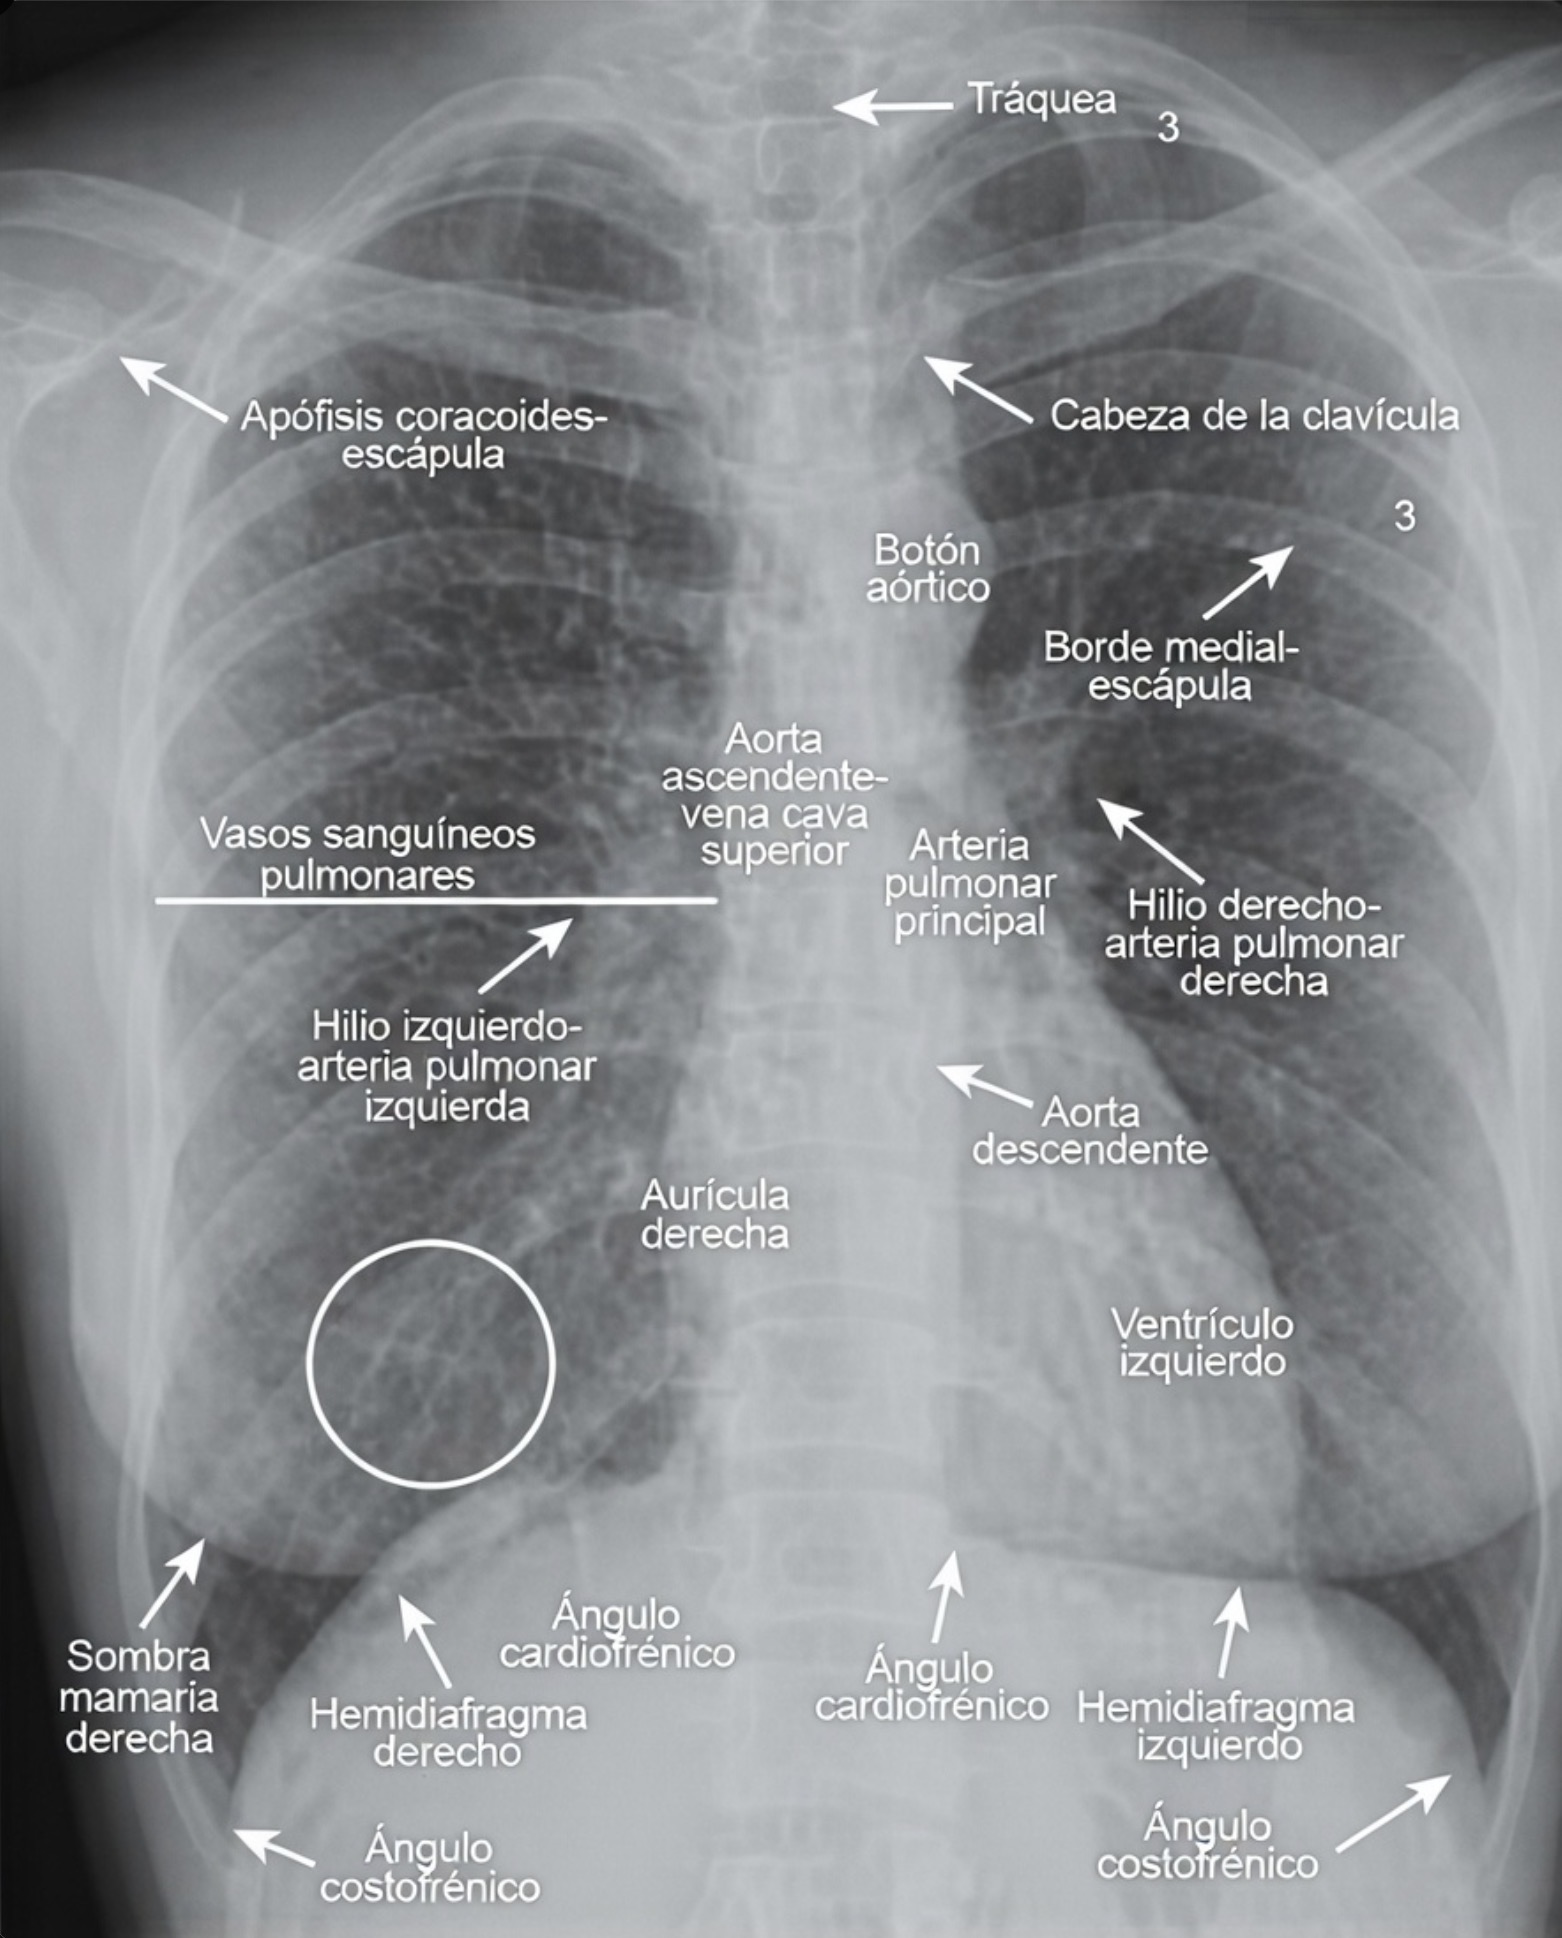

En una radiografía frontal correctamente realizada, la columna vertebral torácica debe visualizarse tenuemente a través de la silueta cardiaca, lo cual indica una penetración radiográfica adecuada. Los ángulos costofrénicos laterales derecho e izquierdo deben observarse agudos y bien definidos, reflejando la ausencia de líquido o engrosamiento pleural significativo.

Un rasgo anatómico importante es que el hilio pulmonar izquierdo suele situarse ligeramente más alto que el derecho. Esta diferencia obedece a la disposición anatómica de las arterias pulmonares y a la relación con el corazón y el arco aórtico. Reconocer esta asimetría como una característica normal evita interpretaciones erróneas.

La mayor parte de las opacidades lineales visibles dentro de los campos pulmonares corresponde a vasos sanguíneos. Estas estructuras se originan en los hilios y se distribuyen hacia la periferia siguiendo un patrón ramificado. A medida que se alejan del centro, disminuyen progresivamente de calibre.

En condiciones normales, no es posible distinguir con exactitud las arterias pulmonares de las venas pulmonares en la radiografía convencional, debido a que ambas presentan densidades y trayectorias similares. Sin embargo, el patrón general de arborización y adelgazamiento progresivo constituye un elemento esencial para reconocer la normalidad.